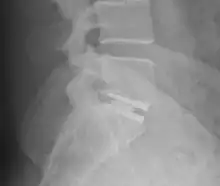

An interbody fusion cage (colloquially known as a "spine cage") is a prosthesis used in spinal fusion procedures to maintain foraminal height and decompression. They are cylindrical or square-shaped devices, and usually threaded. There are several varieties: the Harms cage, Ray cage, Pyramesh cage, InterFix cage, and lordotic LT cage, all of which are made from titanium; the Brantigan cage, made from carbon fibre; and the Cortical Bone Dowel, which is cut from allograft femur. The cages can be packed with autologous bone material in order to promote arthrodesis.[1] Such implants are inserted when the space between the spinal discs is distracted, such that the implant, when threaded, is compressed like a screw. Unthreaded implants, such as the Harms and Pyramesh cages have teeth along both surfaces that bite into the end plates.[1]